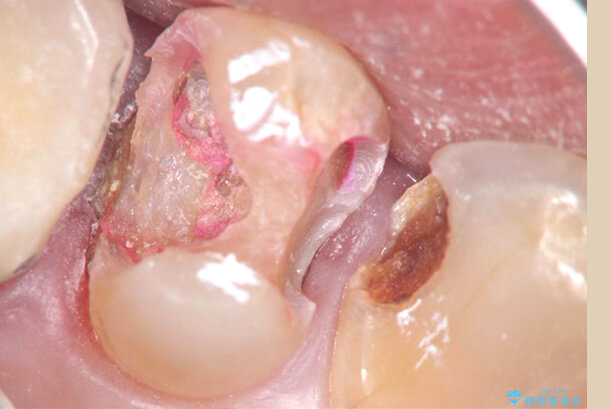

虫歯を除去、根管治療、詰めもの・被せもののセットなど、すべての治療において高倍率な拡大視野で行っております

歯は抜いてしまうと自然に生えてきません。自然歯を一本でも多く残したい、一方的に判断をせず、患者様のご意見を取り入れながら一番良い治療内容を共に探します。